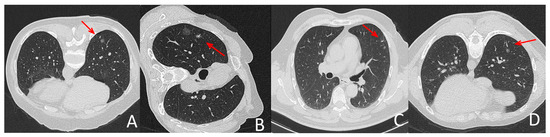

The intraoperative parameters included the patient’s position, diameter of lesion, lesion-pleura distance, shortest distance between the nodule and the puncture needle, distance between the needle tip and the pleura, number of needle insertions and procedure time and localization-related complications and surgery duration. The values for these parameters obtained for each protocol are summarized in Table 2. There were no significant differences between groups (p > 0.05). Figure 1 depicts representative CT-guided lung biopsy images using SDCT versus LDCT.

Figure 1.

Representative localization images with LDCT and SDCT protocols. (A,C) were images during SDCT-guided localization, (B,D) were pictures during LDCT-guided localization. All groups of pictures can clearly show the puncture needle and the lesion. (B,D) showed that the quality of CT pictures in LDCT group meet the demand of localization for lung nodules in different lobes and patients in different position. The arrow indicates the location of the needle tip.